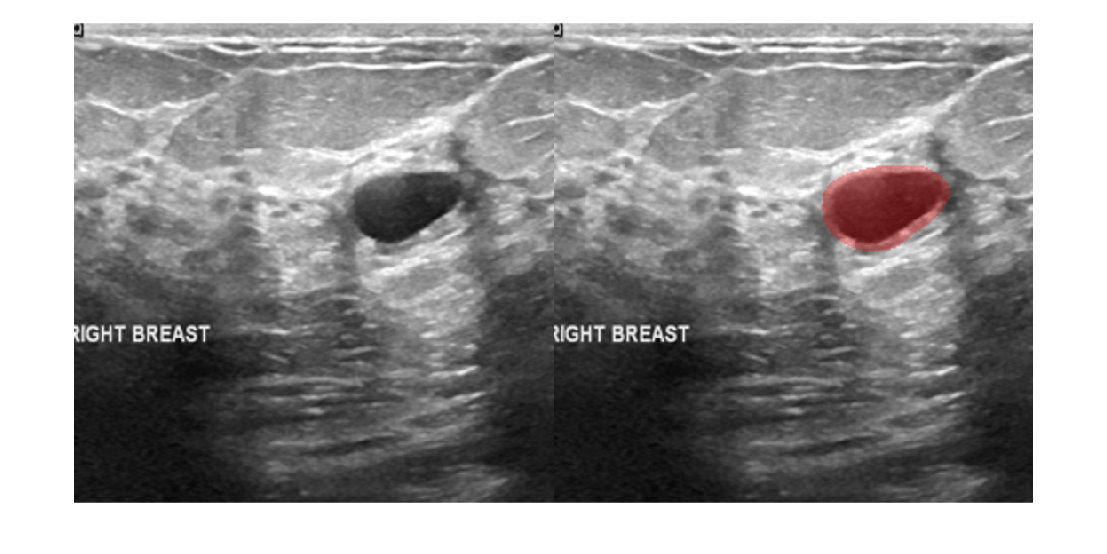

Image segmentation partitions an image into regions. You can perform medical image segmentation using the Medical Segment Anything Model (MedSAM), other deep learning networks, the interactive Medical Image Labeler app, or image processing algorithms. Deep learning networks require Deep Learning Toolbox™ and Computer Vision Toolbox™.

Perform interactive medical image segmentation using Medical Segment Anything Model (MedSAM) and deep learning. (Since R2024b) - Get Started with MedSAM in Medical Image Labeler

This example shows how to interactively segment objects in medical images and in cross-sections of medical volumes using the MedSAM algorithm in the Medical Image Labeler app. (Since R2025a)